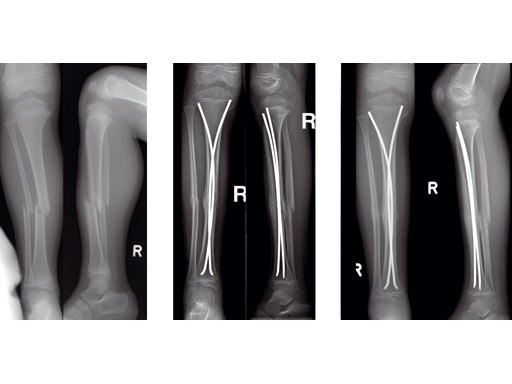

Case of a 8-year old boy with a closed lower leg fracture after football game. Control at 4 and 8 weeks after fractrure.

8-year-old boy.

Case provided by Steffen Berger and Theddy F Slongo, Bern, CH